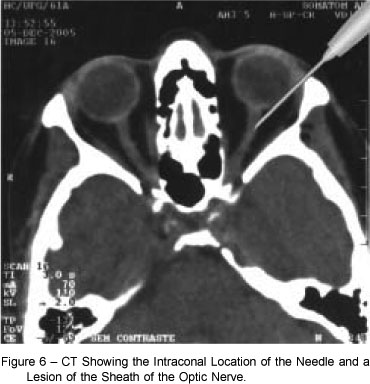

En el estadio terminal de muchas enfermedades oculares, como el glaucoma terminal, cuando se ha perdido la visión y el ojo manifiesta un dolor importante, una de las opciones de tratamiento es la inyección retrobulbar. El objetivo de este estudio, publicado en el número de noviembre de de 2016 de la revista Journal of glaucoma fue evaluar 2 agentes utilizados en las inyecciones retrobulares para aliviar el dolor en ojos amauroticos dolorosos.